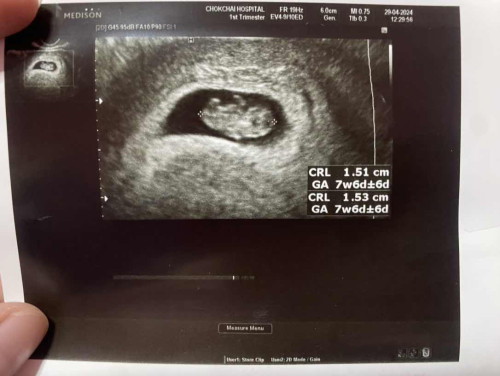

ประจำเดือนล่าสุดเป็น13กุมภา ถ้าคำนวณแล้วนับตามประจำเดือนลูกต้องได้2เดือนจะเข้า3เดือนใช่ไหมค่ะ แต่ที่หมอซาวด์ให้เมื่อวันที่1พฤษภา ได้1เดือนจะเข้า2เดือน สรุปแล้วเราท้องกี่เดือนกี่สัปดาห์ค่ะ

บ้านนี้ คลาดเคลื่อนกัน8วันค่ะแม่ กำหนดคลอดตามประจำเดือน 26/4/67 แต่ตามใบซาวน์ 5/5/67 ค่ะ ส่วนตัวตามใบซาวน์ค่ะ เนื่องจากมีนน. มีความยาวน้องที่เครื่องคาดคะเนมา อาจมีเคลื่อนนิดๆหน่อยๆ